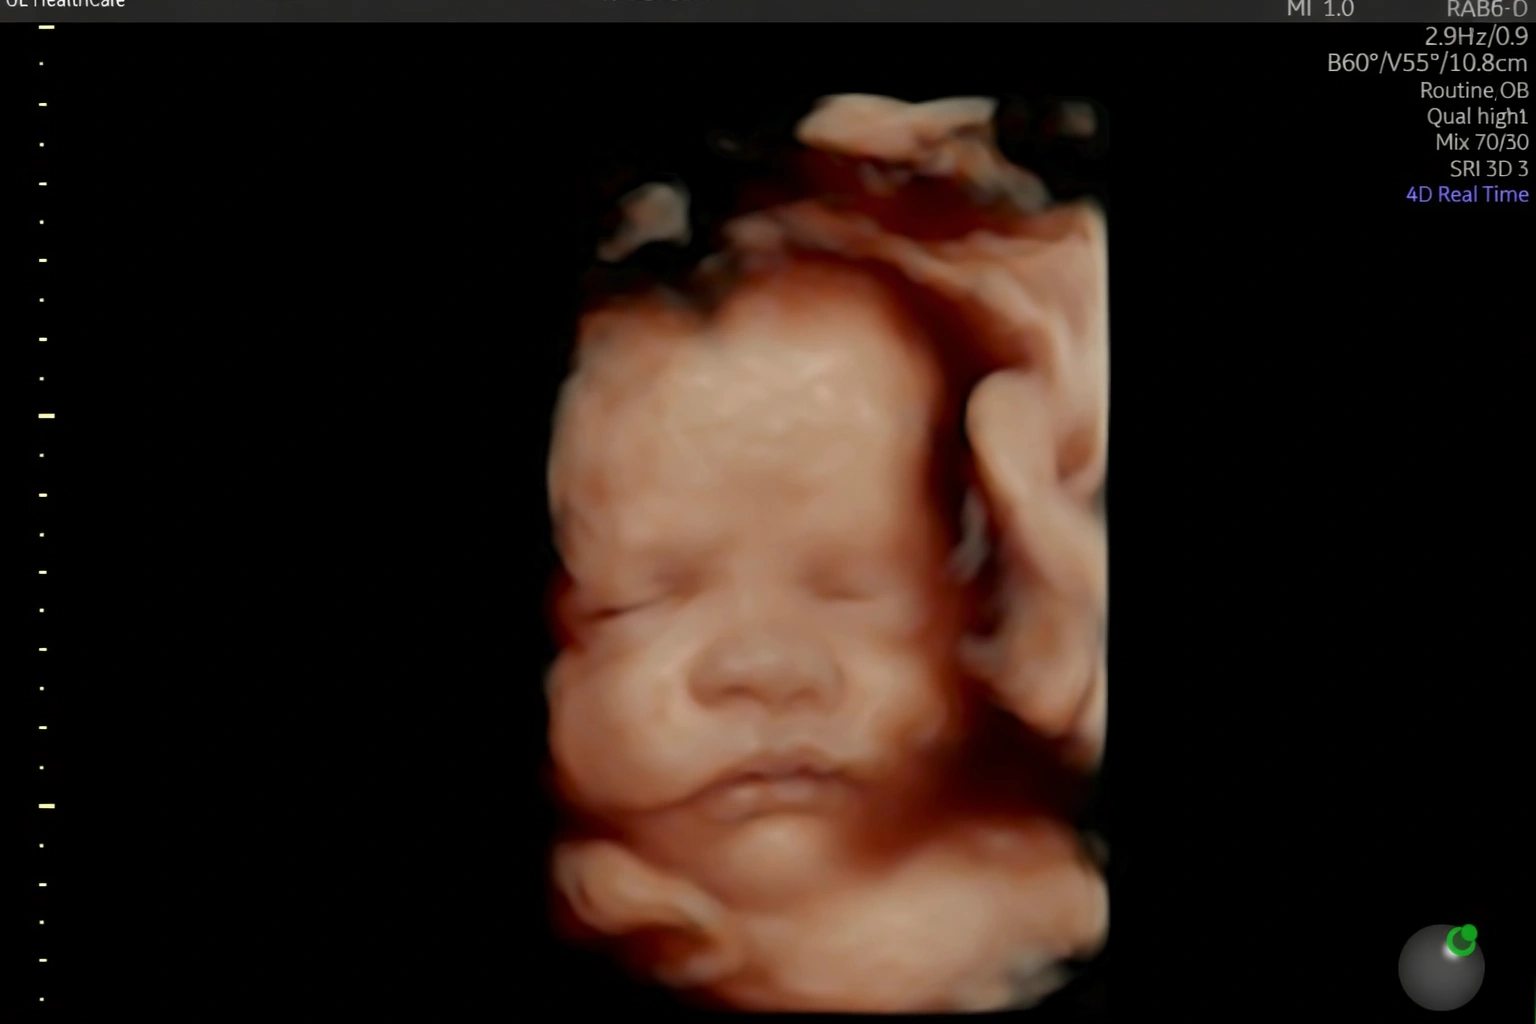

Acompanho detalhadamente toda a evolução do seu bebê ainda na sua barriga.

Realizo diversos tipos de ultrassonografia para garantir que seu bebê chegue ao mundo com saúde.

Estou pronta para realizar diagnósticos precisos sobre como anda a saúde do seu bebê ainda ai dentro da sua barriga. Realizo toda e qualquer tipo de ultrassonografia obstetríca.